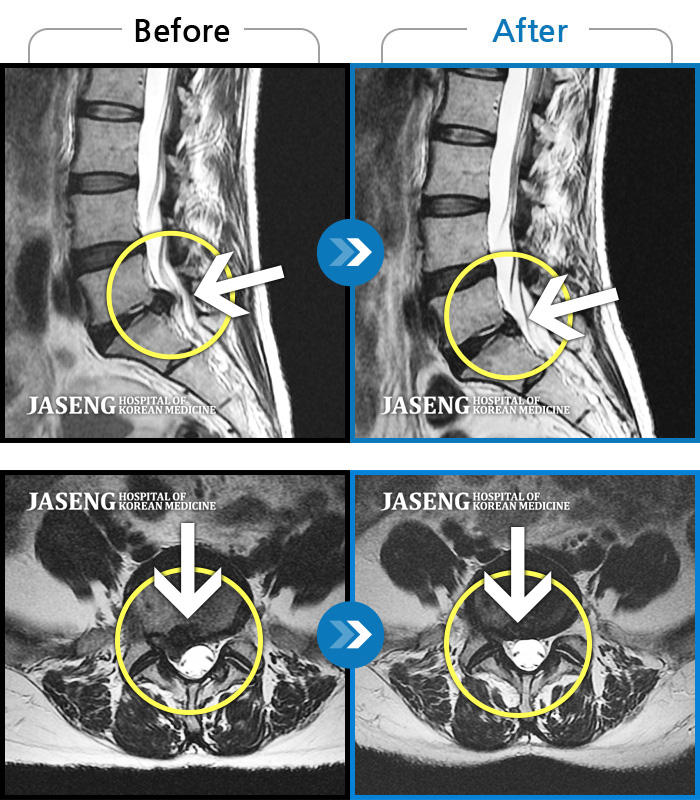

허리 골반 통증이 있고 다리가 저리고 아파 걷기가 힘들다.

2025.02.10 ~ 2025.09.13